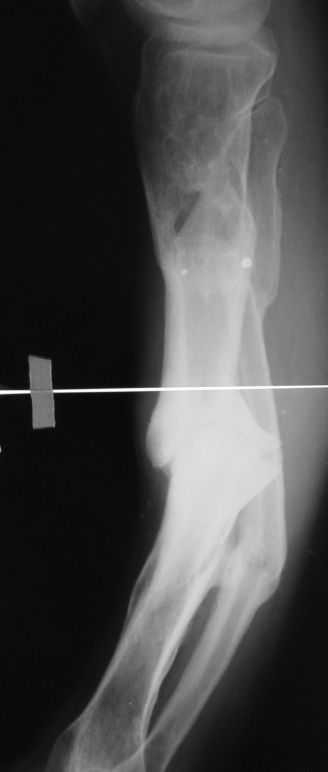

[Ortho] псевдоартроз большеберцовой кости

Александр Николаевич, вечер добрый! Извиняюсь за отсутствие второй прекции. там тоже ещё та деформация! Дозировано исправлять - не уверен что идиально получится выставить по оси дистальный отломок, а смещение даже на кортикал, не влияющие на консолидацию в аппарате, при формировании канала и введении стержня в условиях вальгуса и рекурвации, ну не знаю. Второй вариант, о котором и вы говорите, думаю более предпочтителен. А если делать остеотомию дистальнее ложняка, то что помешает одномоментно откоррегировать? Парез и при аппаратной коррекции с той же долей вероятности может быть.

Имя     : Голень lat.JPG